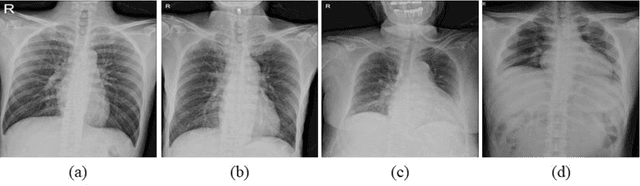

Abstract:Purpose. Imaging plays an important role in assessing severity of COVID 19 pneumonia. However, semantic interpretation of chest radiography (CXR) findings does not include quantitative description of radiographic opacities. Most current AI assisted CXR image analysis framework do not quantify for regional variations of disease. To address these, we proposed a four region lung segmentation method to assist accurate quantification of COVID 19 pneumonia. Methods. A segmentation model to separate left and right lung is firstly applied, and then a carina and left hilum detection network is used, which are the clinical landmarks to separate the upper and lower lungs. To improve the segmentation performance of COVID 19 images, ensemble strategy incorporating five models is exploited. Using each region, we evaluated the clinical relevance of the proposed method with the Radiographic Assessment of the Quality of Lung Edema (RALE). Results. The proposed ensemble strategy showed dice score of 0.900, which is significantly higher than conventional methods (0.854 0.889). Mean intensities of segmented four regions indicate positive correlation to the extent and density scores of pulmonary opacities under the RALE framework. Conclusion. A deep learning based model in CXR can accurately segment and quantify regional distribution of pulmonary opacities in patients with COVID 19 pneumonia.